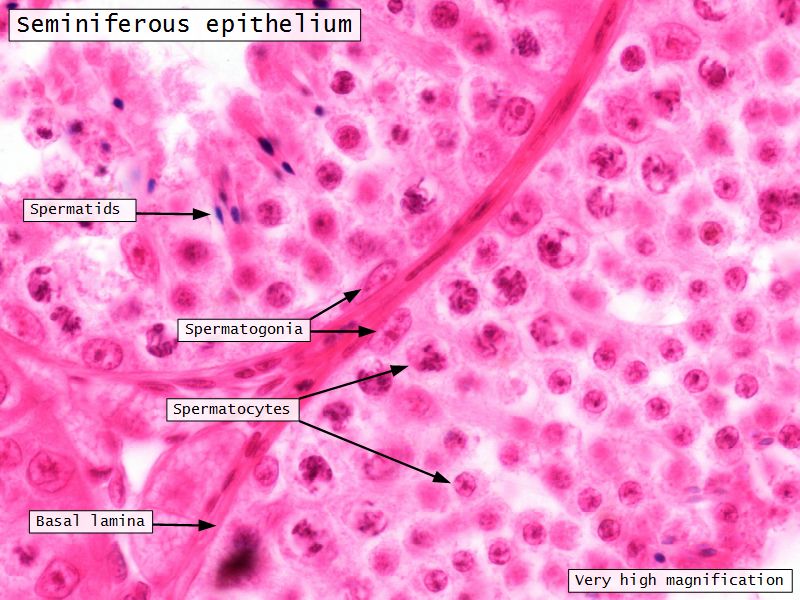

Spermatogenic cells

- Several stages of spermatogenesis

- Spermatogonia

- Primary spermatocytes

- Secondary spermatocytes

- Spermatids

- Spermatozoa

Spermatogonia

- Diploid

- Sits on basal lamina

- 3 types

- Pale type A

- Small, pale nucleus

- Produce pale type A or type B

- Dark type A

- Dark nucleus

- Reserve cell to produce pale type A

- Type B

- Undergo mitosis

- Form primary spermatocytes

Primary spermatocytes

- Largest germ cells

- Diploid

- Undergoes first meiotic division

- Produce secondary spermatocytes

Secondary spermatocytes

- Haploid

- Short stage

- Secondary meiosis

- Produce spermatids

Spermatids

- Haploid

- Small

- Near lumen

- Condensed chromatin in nuclei

- Undergo spermiogenesis